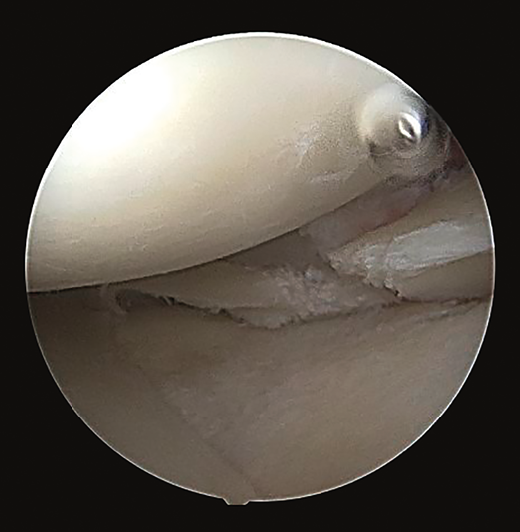

Arthroscopy confirmed the diagnosis by visualizing the avulsed root and bone fragment at medial level (Figure 4A) and the radial lesion of the external root (Figure 5). Palpation of both roots evidenced clear instability. The ACL was greatly affected, with subtotal rupture, while the PCL presented correct stability in response to palpation and testing.

Figure 5. Arthroscopic view from the anterolateral portal, identifying the radial lesion of the root of the external meniscus.